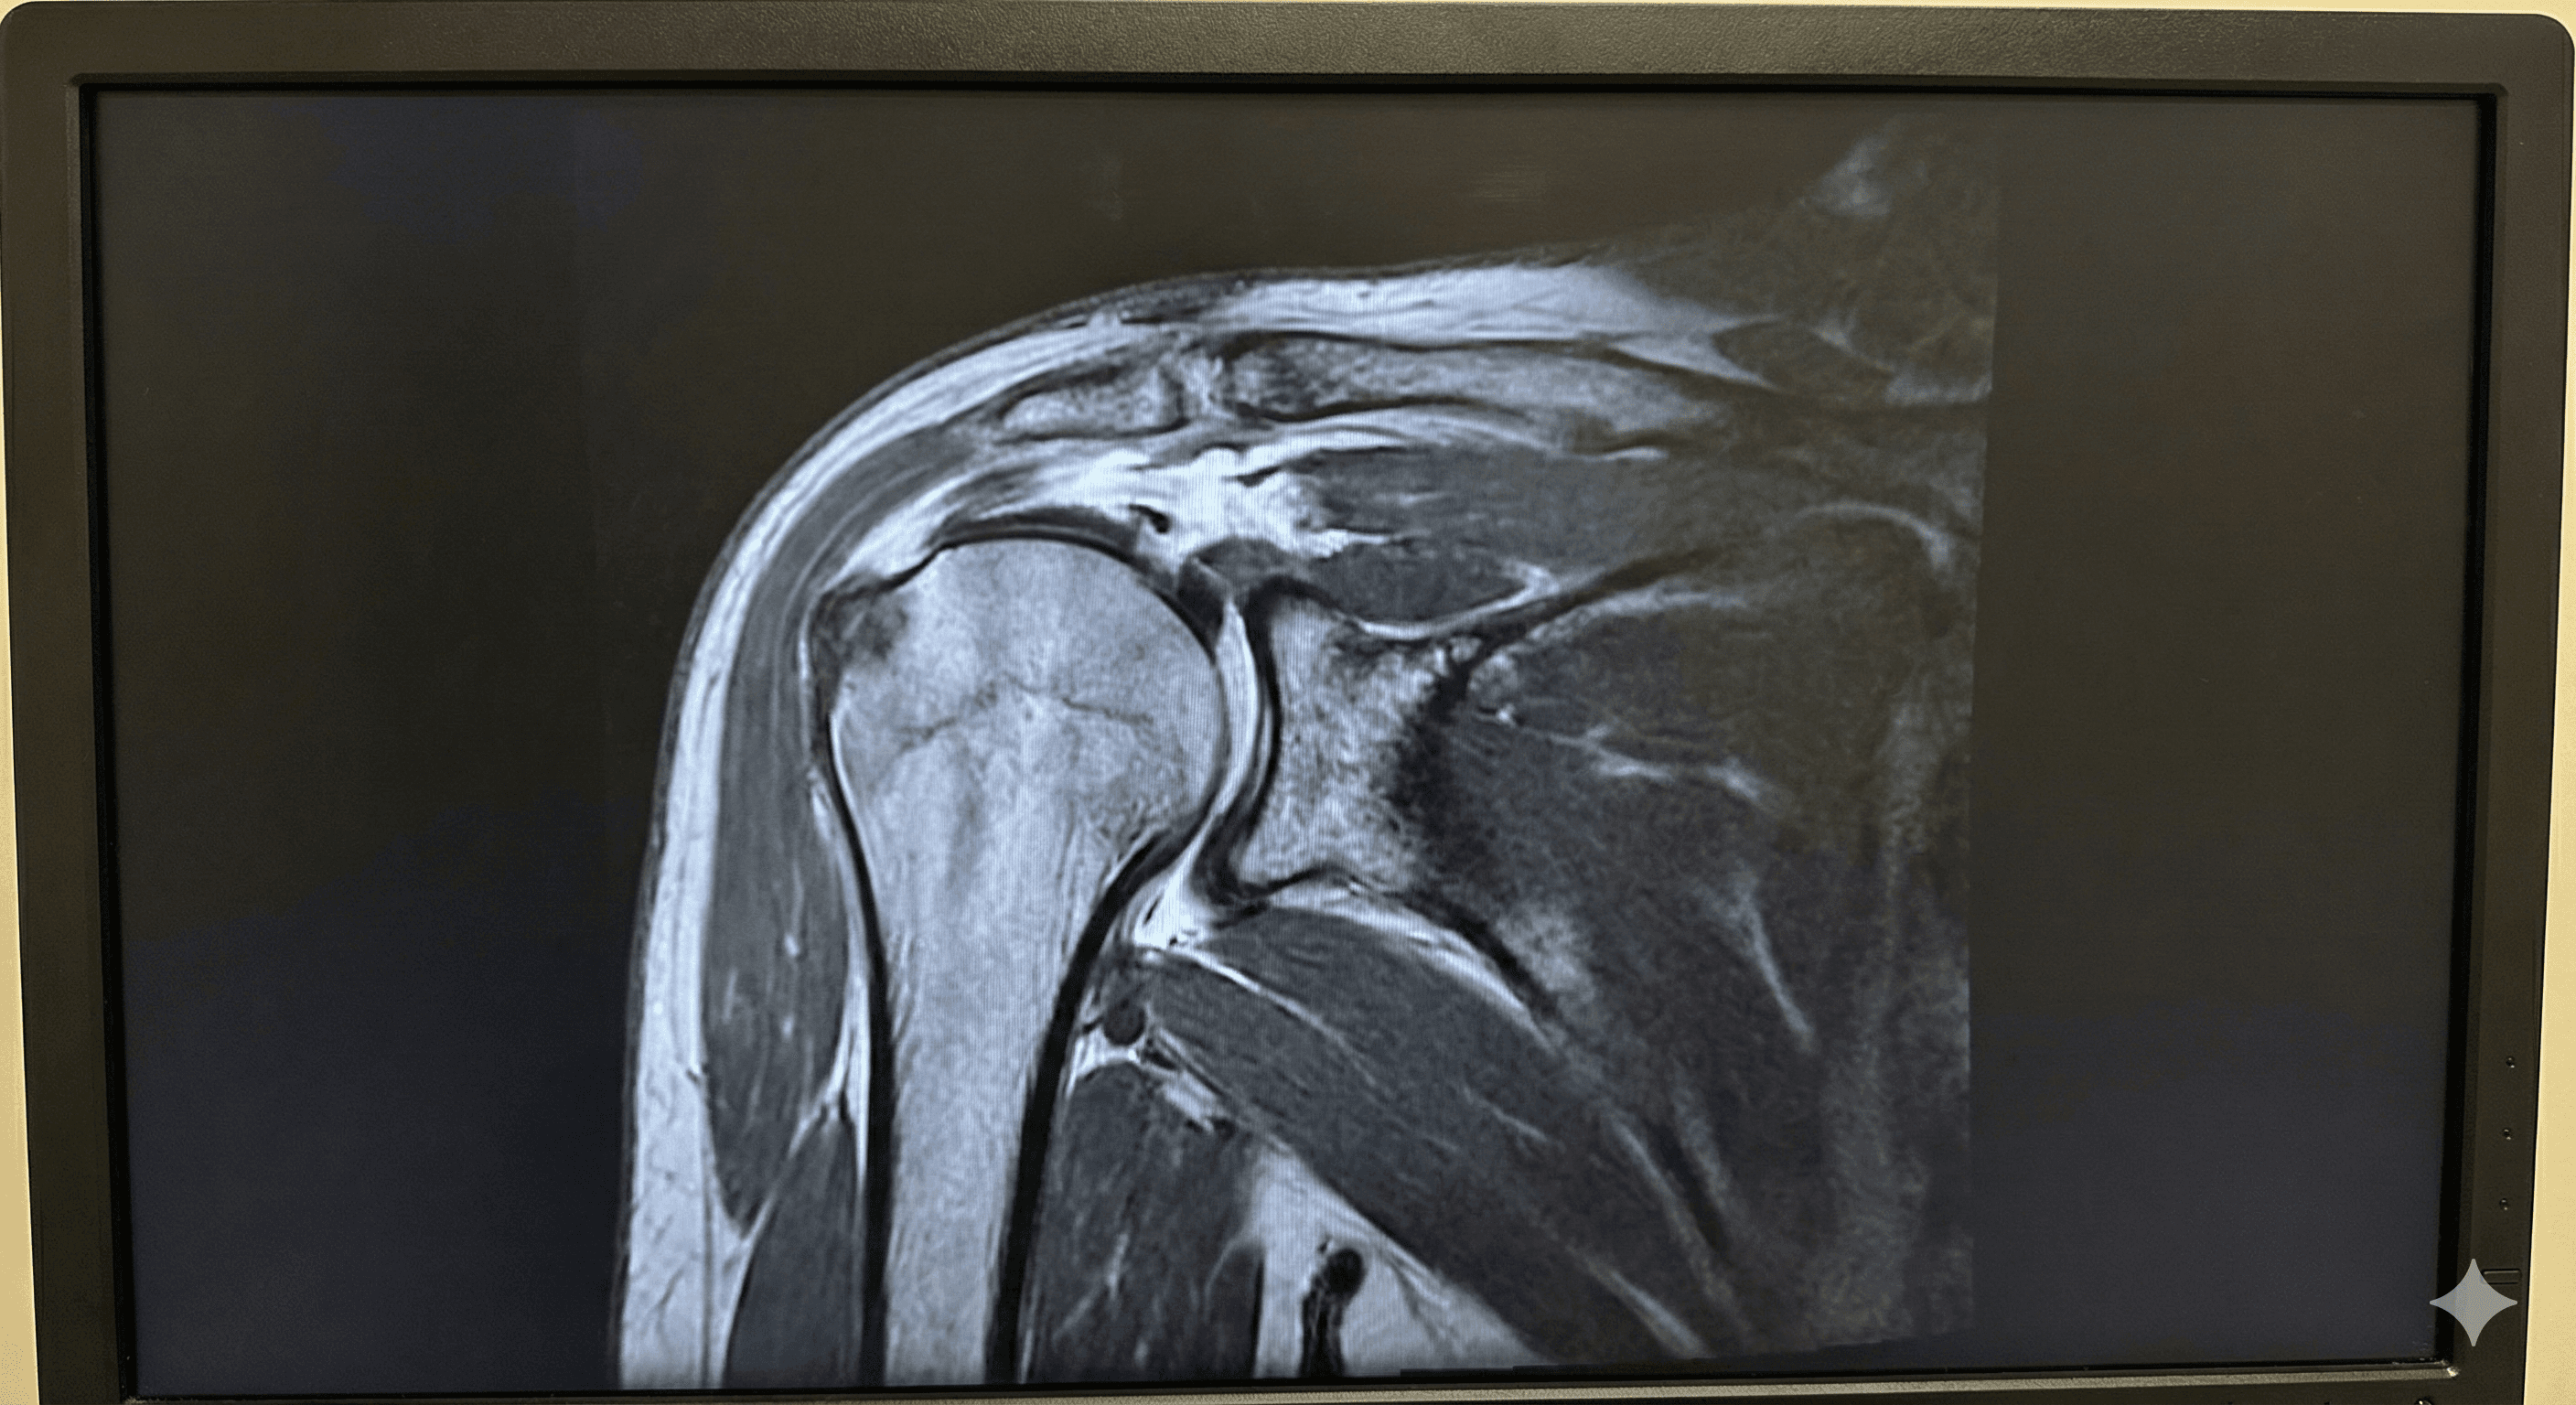

Desgarro o inflamación de los músculos y tendones que rodean el hombro.

Leer más